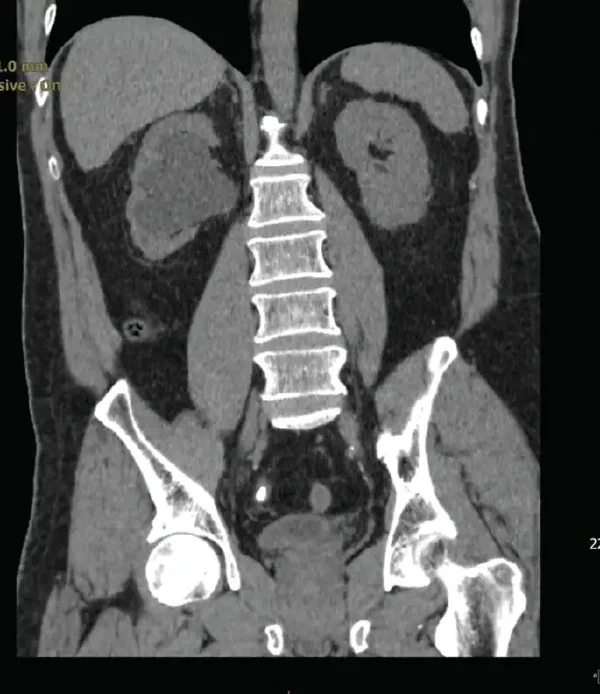

泌尿系结石是尿液中的矿物质和酸性盐类浓度过高而沉积形成的“小体积硬块”。它可能形成在肾脏内部,随后掉落到输尿管中,甚至进入膀胱和尿道。根据成分不同,结石的种类分为草酸钙结石、尿酸结石、磷酸钙结石及胱氨酸结石等。形成的具体原因可能涉及代谢紊乱、饮水不足、饮食结构不均衡、反复感染等。

这种“小石头”会对人体造成多大的影响呢?最直接的危害就是剧烈的疼痛。通常,患者会感受到一侧(多数为左侧或右侧)的腰腹部剌痛,疼痛可能向前放射至腹部甚至大腿根部。这种疼痛为间歇性阵发性,据说疼痛等级能与产痛媲美。此外,结石的位置和大小决定了它的危害程度,例如较大的结石可能完全阻塞输尿管出口,导致尿液难以排出,可能引发肾积水和感染。长期的尿路阻塞可能最终损害尿路细胞甚至诱发肾衰竭。